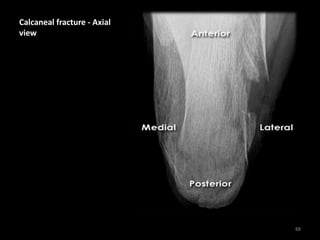

Calcaneal fracture - Axial

view

Loss of smooth cortical

edge (orange line)